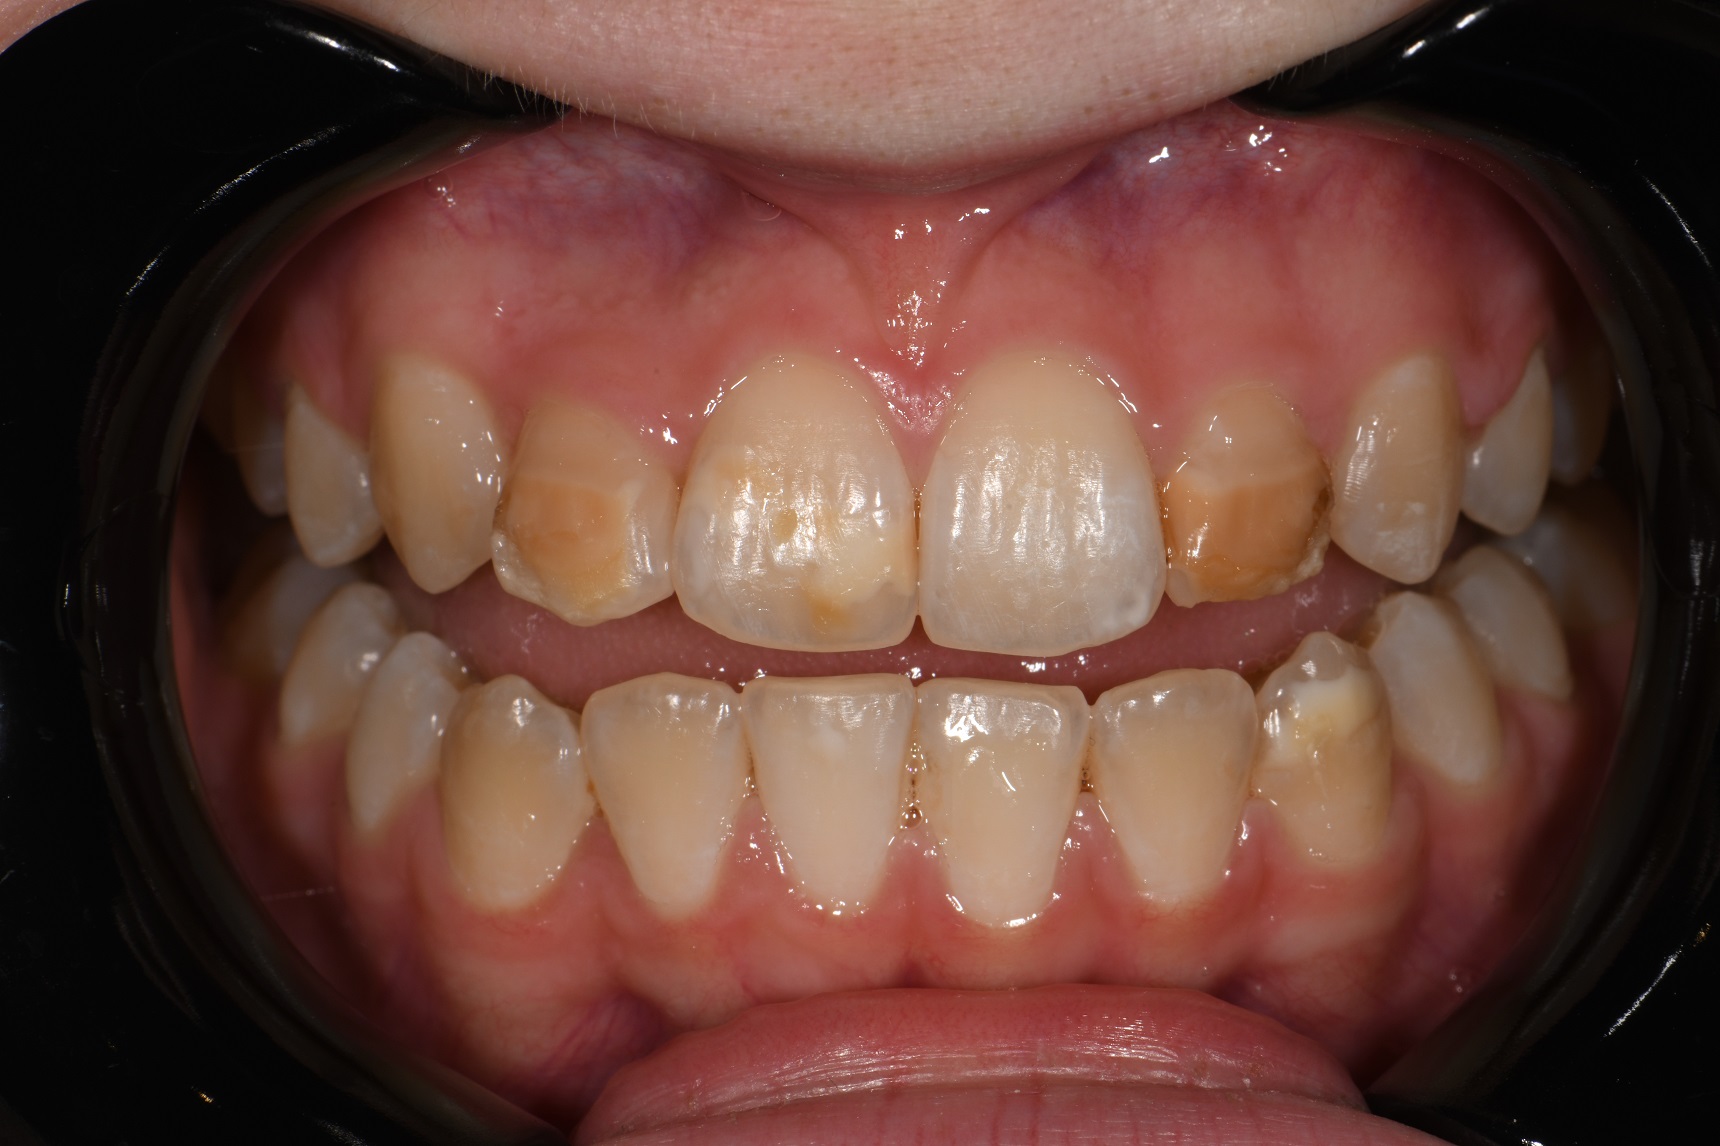

From smiledentallounge.com

ICON Resin Infiltration The Smile Dental Lounge Dental Clinic Johor Where Is Resin Infiltration Most Successfully Used They were informed that the process may need to be repeated several times in order to treat deeper lesions. resin infiltration is a minimally invasive technique to treat mild hypomineralized lesions. the principle of resin infiltration is to perfuse the porous enamel with resin by capillary action, thereby arresting lesion. resin infiltration seems to be a clinically. Where Is Resin Infiltration Most Successfully Used.